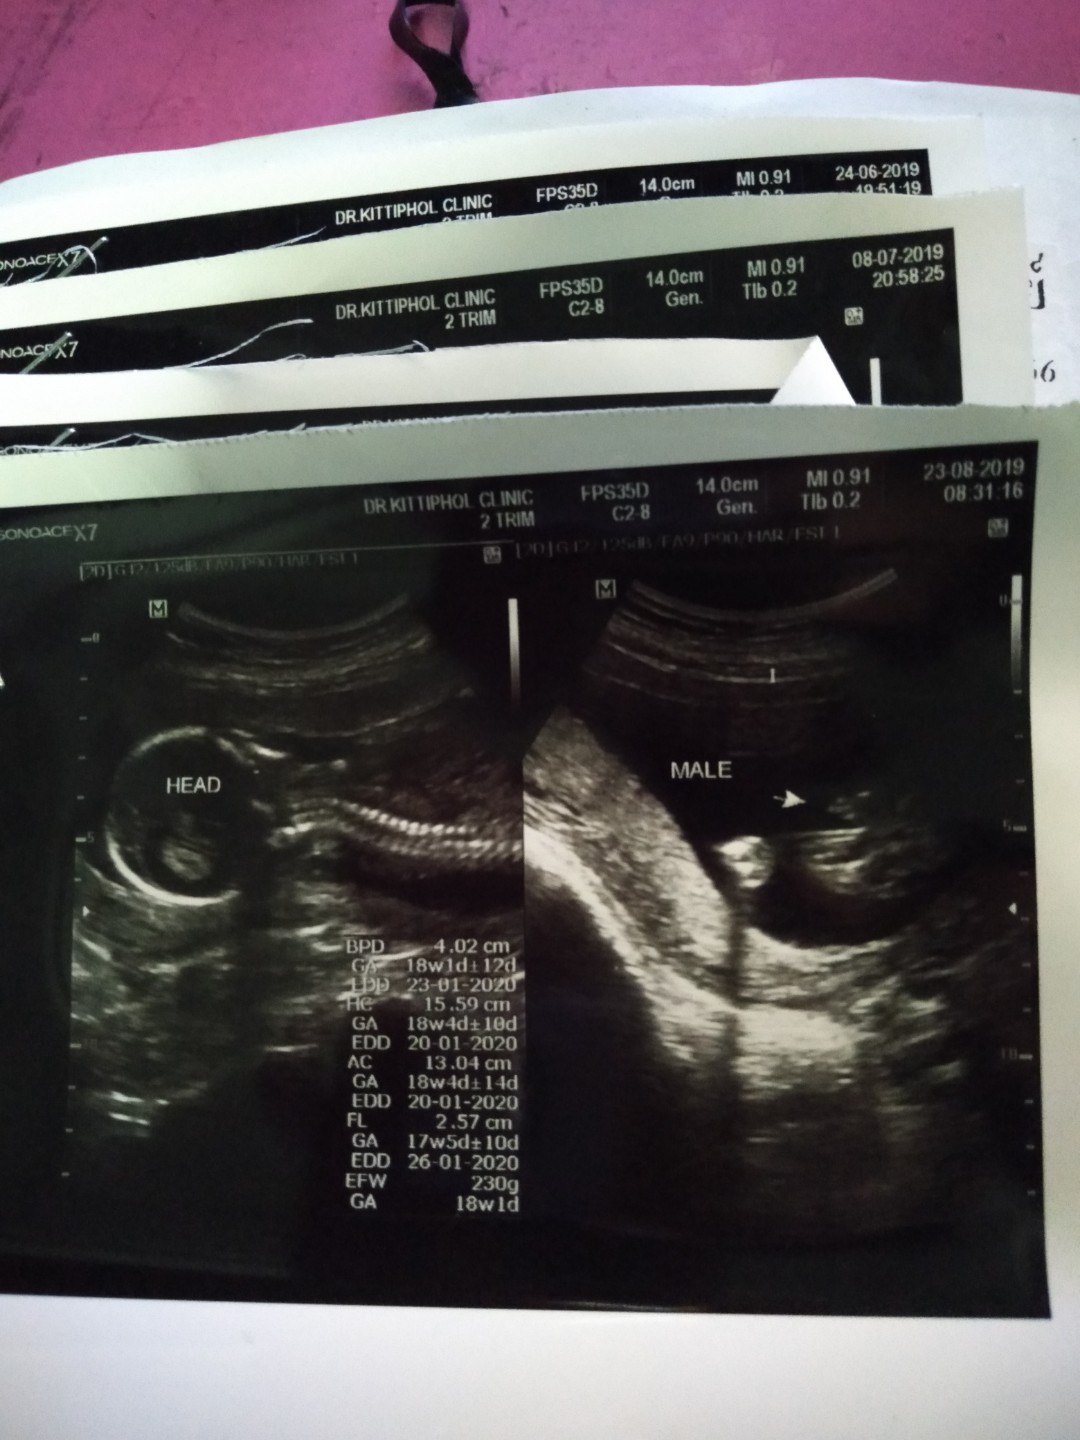

7มค จ้า ได้ลูกชายจ้า

25 มกราคม เพศชายจ้า

23มกราคม63..ลูกชายคะ

20มกราผู้ชายจร้า